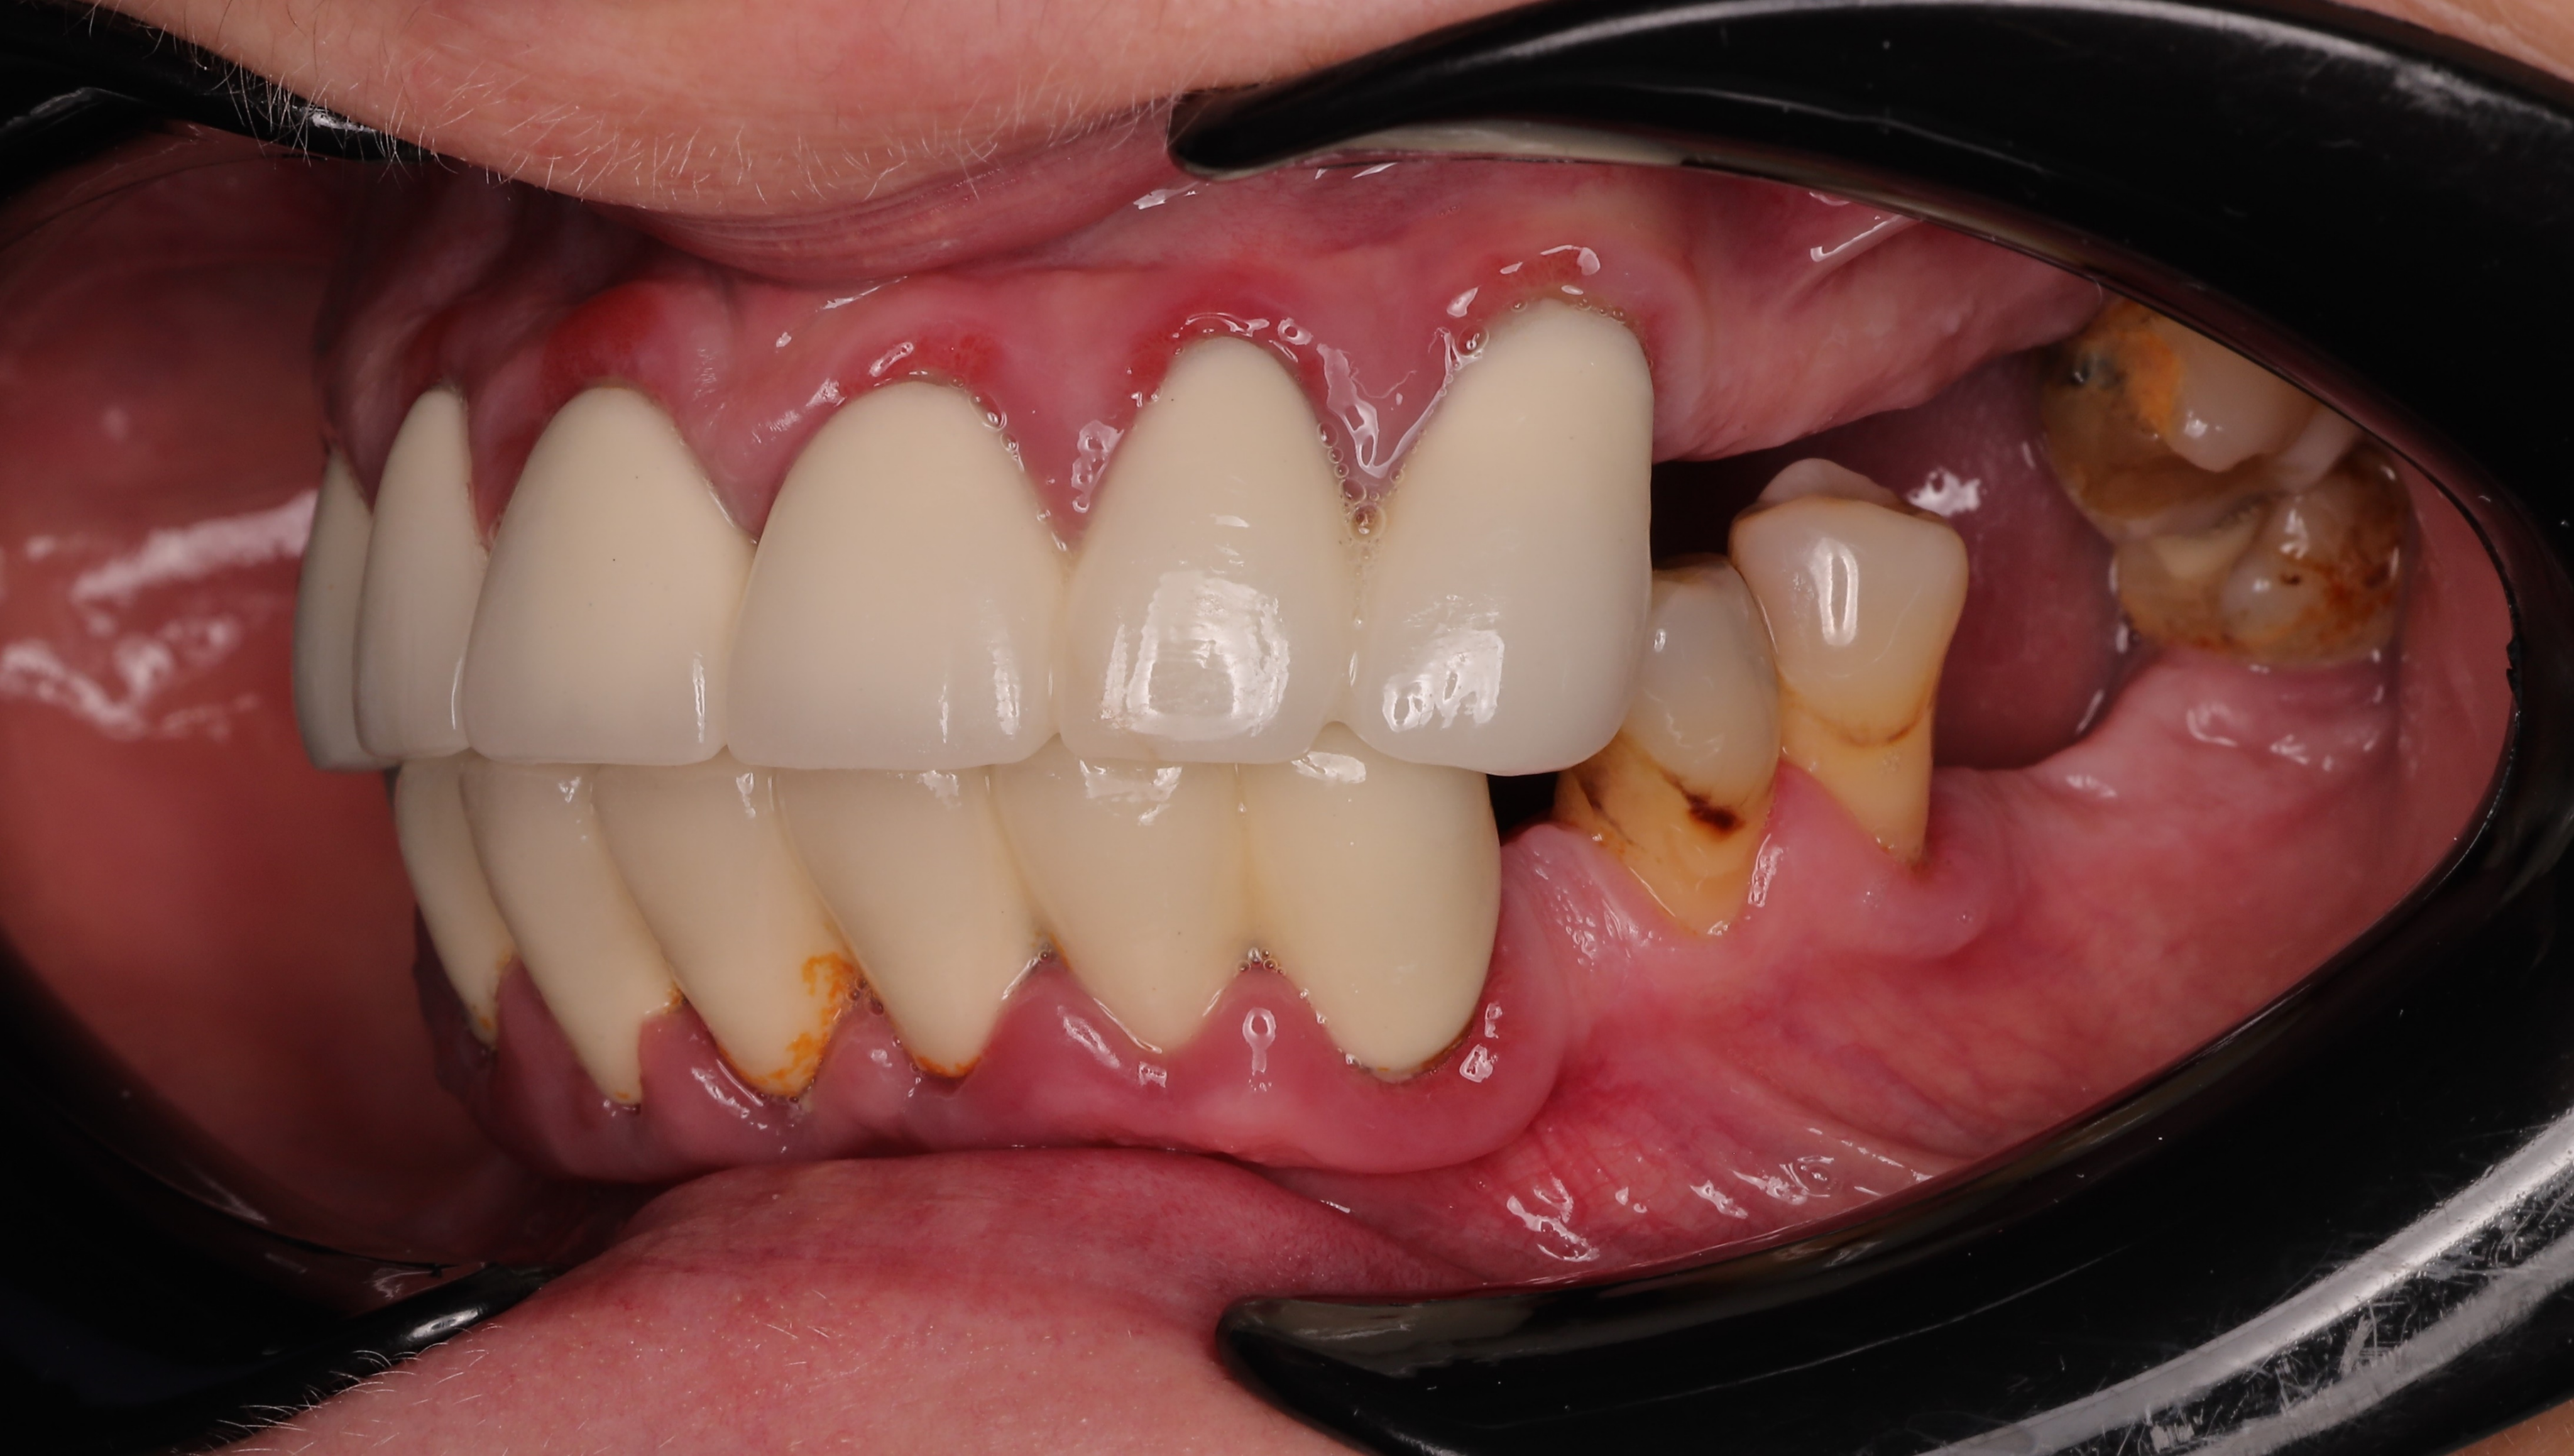

A 52-year-old female with Type II diabetes presented with failing dentition, characterized by generalized mobility, gingival bleeding, and poorly fitting dentures. Clinical challenges included arch deformities and severe posterior maxillary bone deficiency due to advanced sinus pneumatization. To meet the patient's request for immediate function and esthetics, a "teeth-in-a-day" protocol was implemented, involving full-arch extractions, IPG scanning, immediate implant placement, and the delivery provisional restoration on the day of surgery.

At the six-month follow-up, the patient reported high satisfaction with the functional and aesthetic performance of the provisional restorations. Clinical examination following the removal of the provisionals revealed optimal soft tissue healing and well-preserved gingival architecture. Notably, the Root Shield sites at 13, 12, and 23 successfully maintained the buccal ridge contour, while radiographic evaluation (OPTG) confirmed complete osseointegration of all implants, including the pterygoid fixtures at sites 17 and 27.